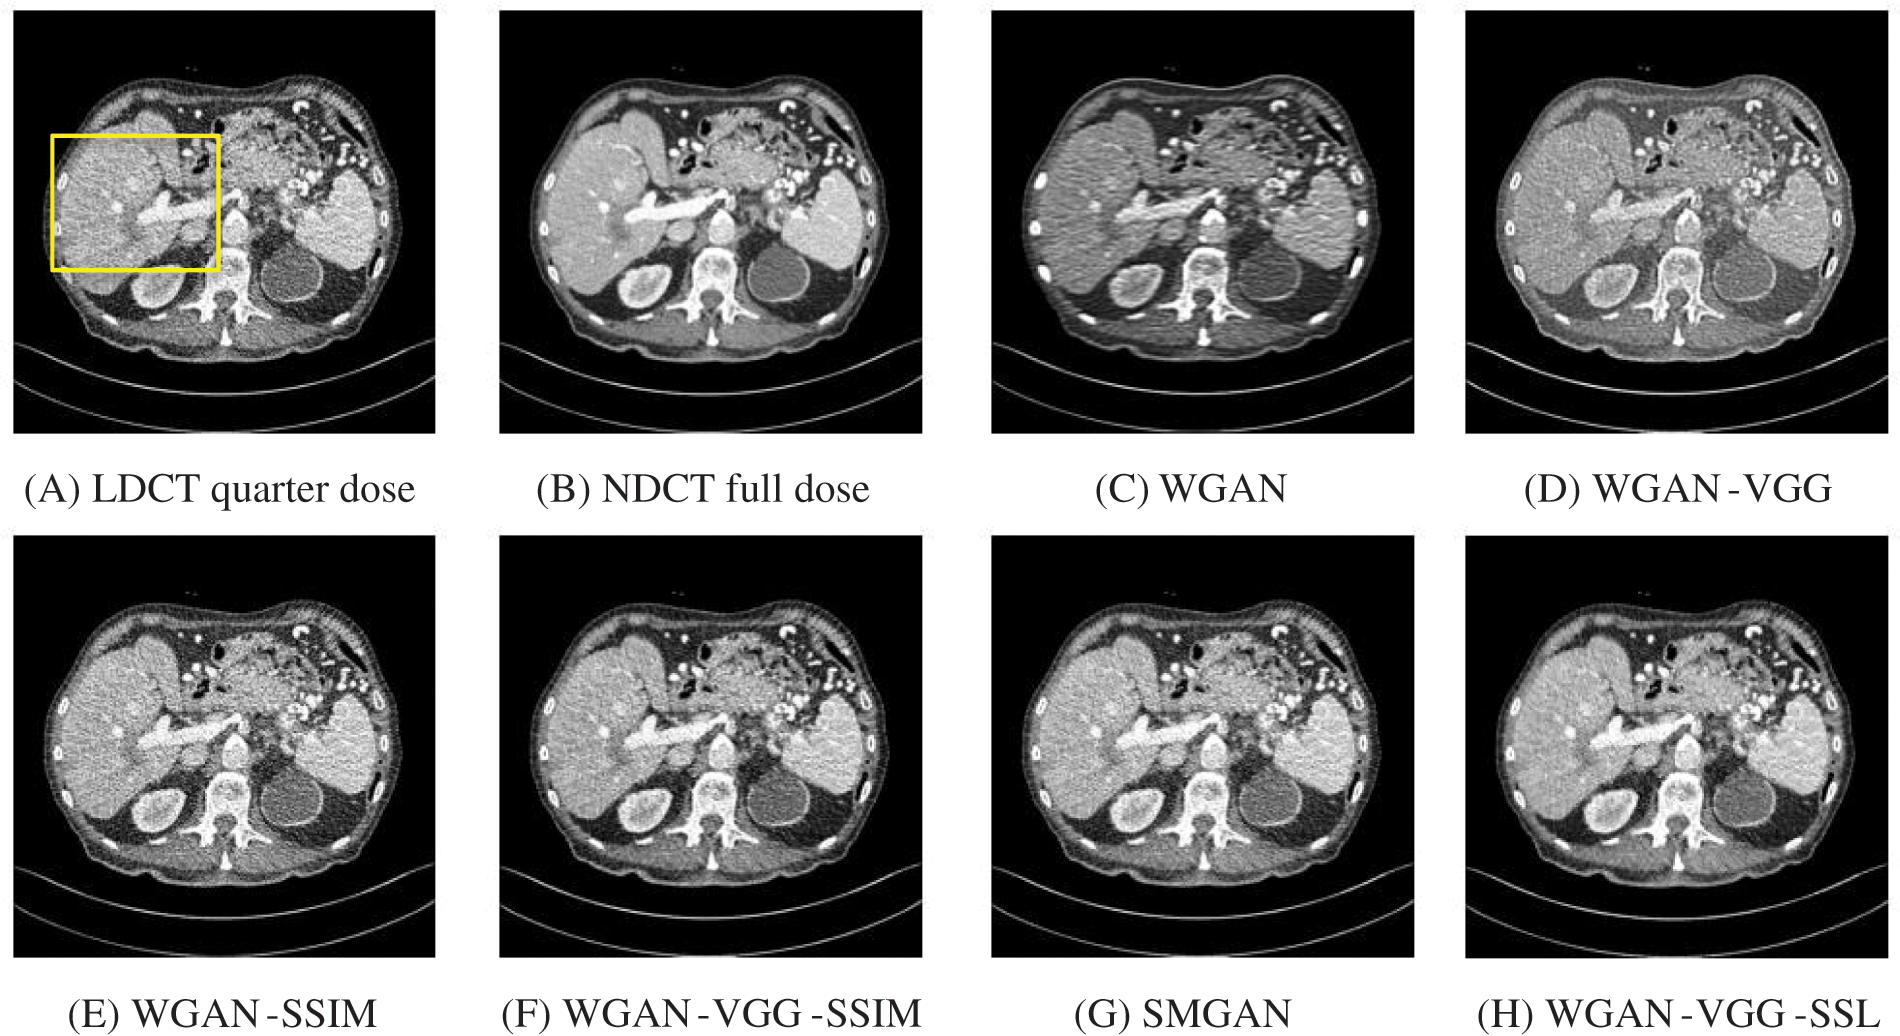

To assess the efficiency of the variant loss function, this work trained the proposed models (WGAN-SSIM, WGAN-VGG-SSIM, WGAN-VGG-SSL), and also trained the best-known models such as WGAN [30], WGAN-VGG [14], and SMGAN [25]. We used two examples of a CT image that were taken from the testing data folders ‘L067’ and ‘L506’, and took a zoomed representative slice of each example to show more structure details as a yellow rectangle in Figs. 2 and 3, and Figs. 6 and 7 respectively. The experimental results showed that generated images using WGAN have a more blurred appearance than the other models. Even though WGAN reduced the white artifact, the produced images are not considerably enhanced compared to NDCT images; some structures are over-smoothed, as shown in Fig. 7C with a red arrow. WGAN cannot preserve the edge details as shown in Figs. 2C and 3C, in which generated images lost the textures of the liver. WGAN-VGG has a few white structures. Although it produced images that were sharper than WGAN, it distorted some of the fine structure details. WGAN-VGG has low contrast as shown in Figs. 2D, 3D, and 7D with a yellow arrow; the performance of WGAN has not improved because it just moves from the noise distribution to the free distribution and does not depend on any human perceptual knowledge. On the other hand, perceptual loss is included in WGAN-VGG. WGAN-SSIM achieved visually better than WGAN and WGAN-VGG and preserved features as marked by the yellow arrow in Figs. 6E and 7E. It is noticed that the three models (WGAN-VGG-SSL, SMGAN, and WGAN-VGG-SSIM) preserved the fine image and retained informative details as shown in Figs. 6F–6H, and 7F–7H by red and yellow arrows. Finally, WGAN-VGG-SSL suppressed noise and artifacts, and generated images that are close to NDCT images; it also kept the structural features better than the other methods and determined the lesion location as pointed out by the red dashed circle in Fig. 6H. In conclusion, WGAN-VGG-SSL achieved better informative feature preservations and visual quality than other WGAN methods.

Figure 2: The generated images from the testing data ‘L067’ on CPU at 2000 iterations

Figure 3: The generated images from the testing data ‘L506’ on CPU at 2000 iterations